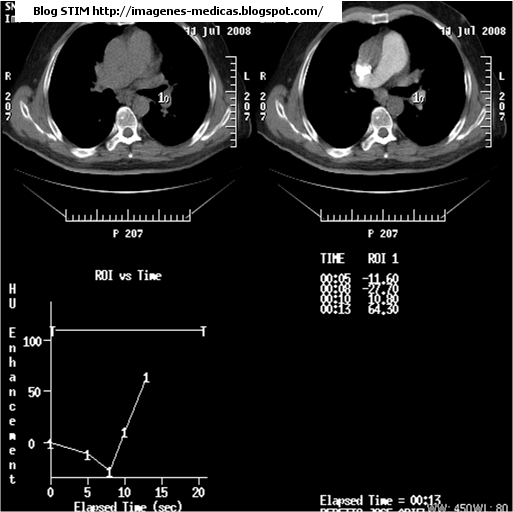

Sobre la pantalla, al momento del monitoreo de la inyección tendremos un curva densidad-tiempo y las imágenes axiales con vision directa de la opacificación de los vasos. (Fig1)

Fig1Arriba izquierda: imagen axial con una ROI en la arteria pulmonar izquierda (se puede colocar en el tronco).

Arriba derecha: imagen axial con la imágen salvada al momento de iniciar la fase de scan.Observar el tronco de la pulmonar con realce. Este estudio salió un poco contaminado. Para ver el momento exacto para iniciar el scan ver la figura2

Abajo izquierda: Gráfico realce-tiempo. Esto depende de la buena ubicación de la ROI. En este caso no se da importancia al gráfico; pero si a la imágen axial de arriba a la derecha para iniciar el barrido.

Abajo derecha: Se realizó un corte axial a los 5 seg de iniciada la inyección, otro a los 8,10 y finalmente a los 13 seg donde se decidió iniciar la adquisisión, a eso se le suman unos 5 a 10 seg de delay diagnóstico.